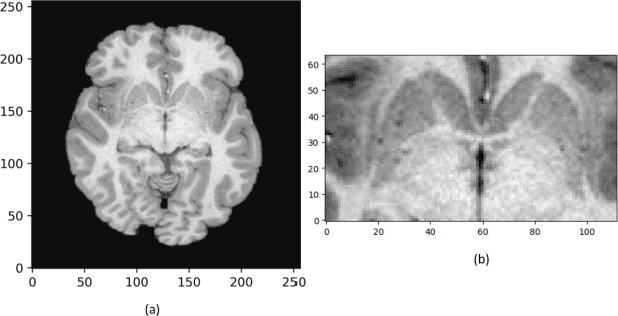

In recent years, Deep Learning (DL) has shown promising results in conducting AI tasks such as computer vision and image segmentation. Specifically, Convolutional Neural Network (CNN) models in DL have been applied to prevention,detection, and diagnosis in predictive medicine. Image segmentation plays a significant role in disease detection and prevention.However, there are enormous challenges in performing DL-based automatic segmentation due to the nature of medical images such as heterogeneous modalities and formats, insufficient labeled training data, and the high-class imbalance in the labeled data. Furthermore, automating segmentation of medical images,like magnetic resonance images (MRI), becomes a challenging task. The need for automated segmentation or annotation is what motivates our work. In this paper, we propose a fully automated approach that aims to segment the human claustrum for analytical purposes. We applied a U-Net CNN model to segment the claustrum (Cl) from a MRI dataset. With this approach, we have achieved an average Dice per case score of 0.72 for Cl segmentation, with K=5 for cross-validation. The expert in the medical domain also evaluates these results.